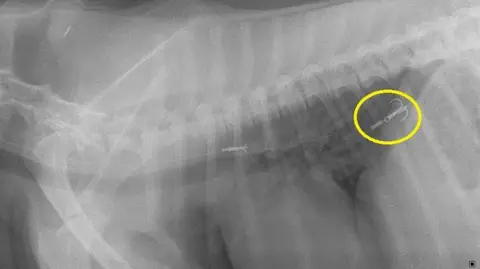

This week, Iran appointed a new supreme leader, a German city had to be evacuated when a large WW2 bomb was found, and the UK got a first listen to its unusual entry for this year's Eurovision song contest. But how much attention did you pay to what else happened in the world over the past seven days? Quiz collated by Ben Fell. Fancy some more? Try last week's quiz, or have a go at something from the archives. They treated three dogs for fish hook injuries in just one month - including a spaniel called Chip from Stranraer. Lynn Symphorien said Guernsey animals are now recognised for their quality in the UK. People Failsworth are continuing to search for the last of the dogs that were in the van at the time. Lurcher-collie cross Storm fell off the cliff ending up on a ledge 20m (66ft) below. Scientists have found further evidence that pet flea treatments are widespread in rivers across the UK.